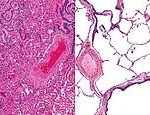

Female vaper, 49, suffers an incurable lung disease found in metal factory workers

A vaper has been diagnosed with an incurable form of lung scarring typically found in metal factory workers.

Doctors say the rare disease was likely...